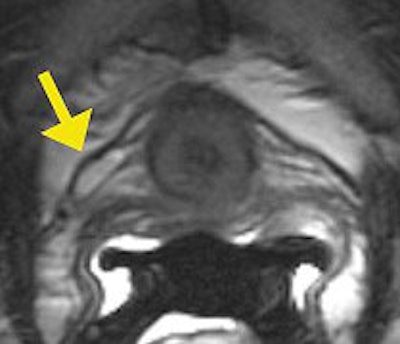

| Intraurethral MR shows details of urethra sphincter muscles (outer T2 dark striated muscle and inner T2 bright smooth muscle). Image courtesy of Dr. Katarzyna J. Macura, Ph.D., Johns Hopkins University. |